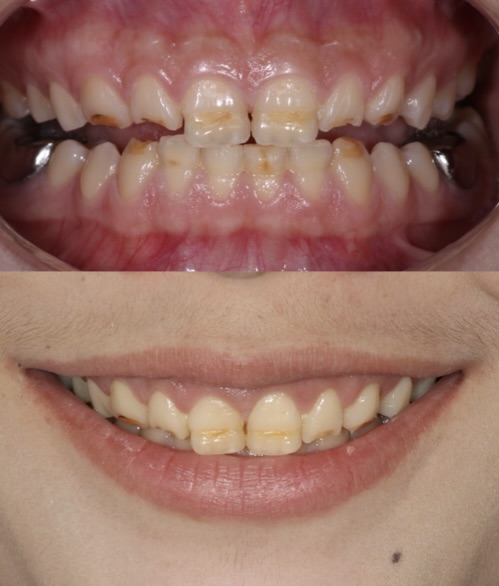

Before

After

Braces - Molar closing

Orthodontic treatment for a patient with a narrow maxilla and missing lower first molars bilaterally. Treatment included arch expansion, molar protraction for space closure, and full arch alignment to restore function and aesthetics. Case completed by the Moral Dental Team.